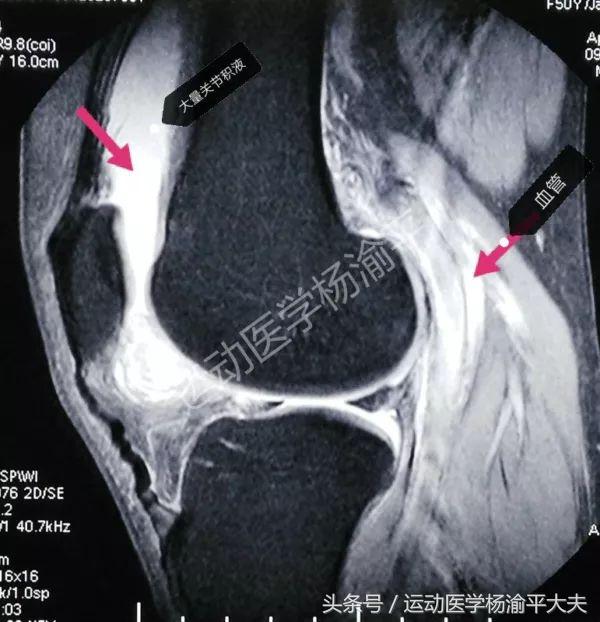

一般做关节的手术,关节里面都会有出血,那么血液在核磁上跟水是一样的,无法区分,也就形成了核磁里面的积液。这也是积液在核磁共振里面的特点。尤其是在T2像(大家懂不懂这个没关系,知道就行),T2像上我们的组织一般是偏深色或者黑色的,尤其是骨头和肌腱(见图一或图二)有意思的是,白色的就是液体。

(图一)

不难发现,特别亮的信号,就是积液。图二这个病人是关节滑膜性疾病,它会渗出大量的积液,所以是这种表现。但同时能看见这张图里我用箭头标识指的是血管里面流的是血液也就是水,也是液体,所以在核磁上同样是跟积液完全一样的高信号。